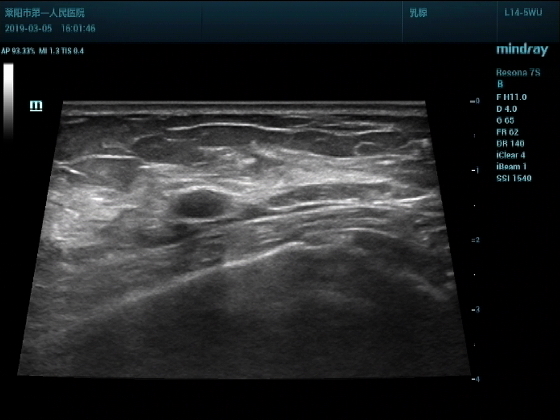

超声入门贴994--乳腺纤维瘤(弹性成像)